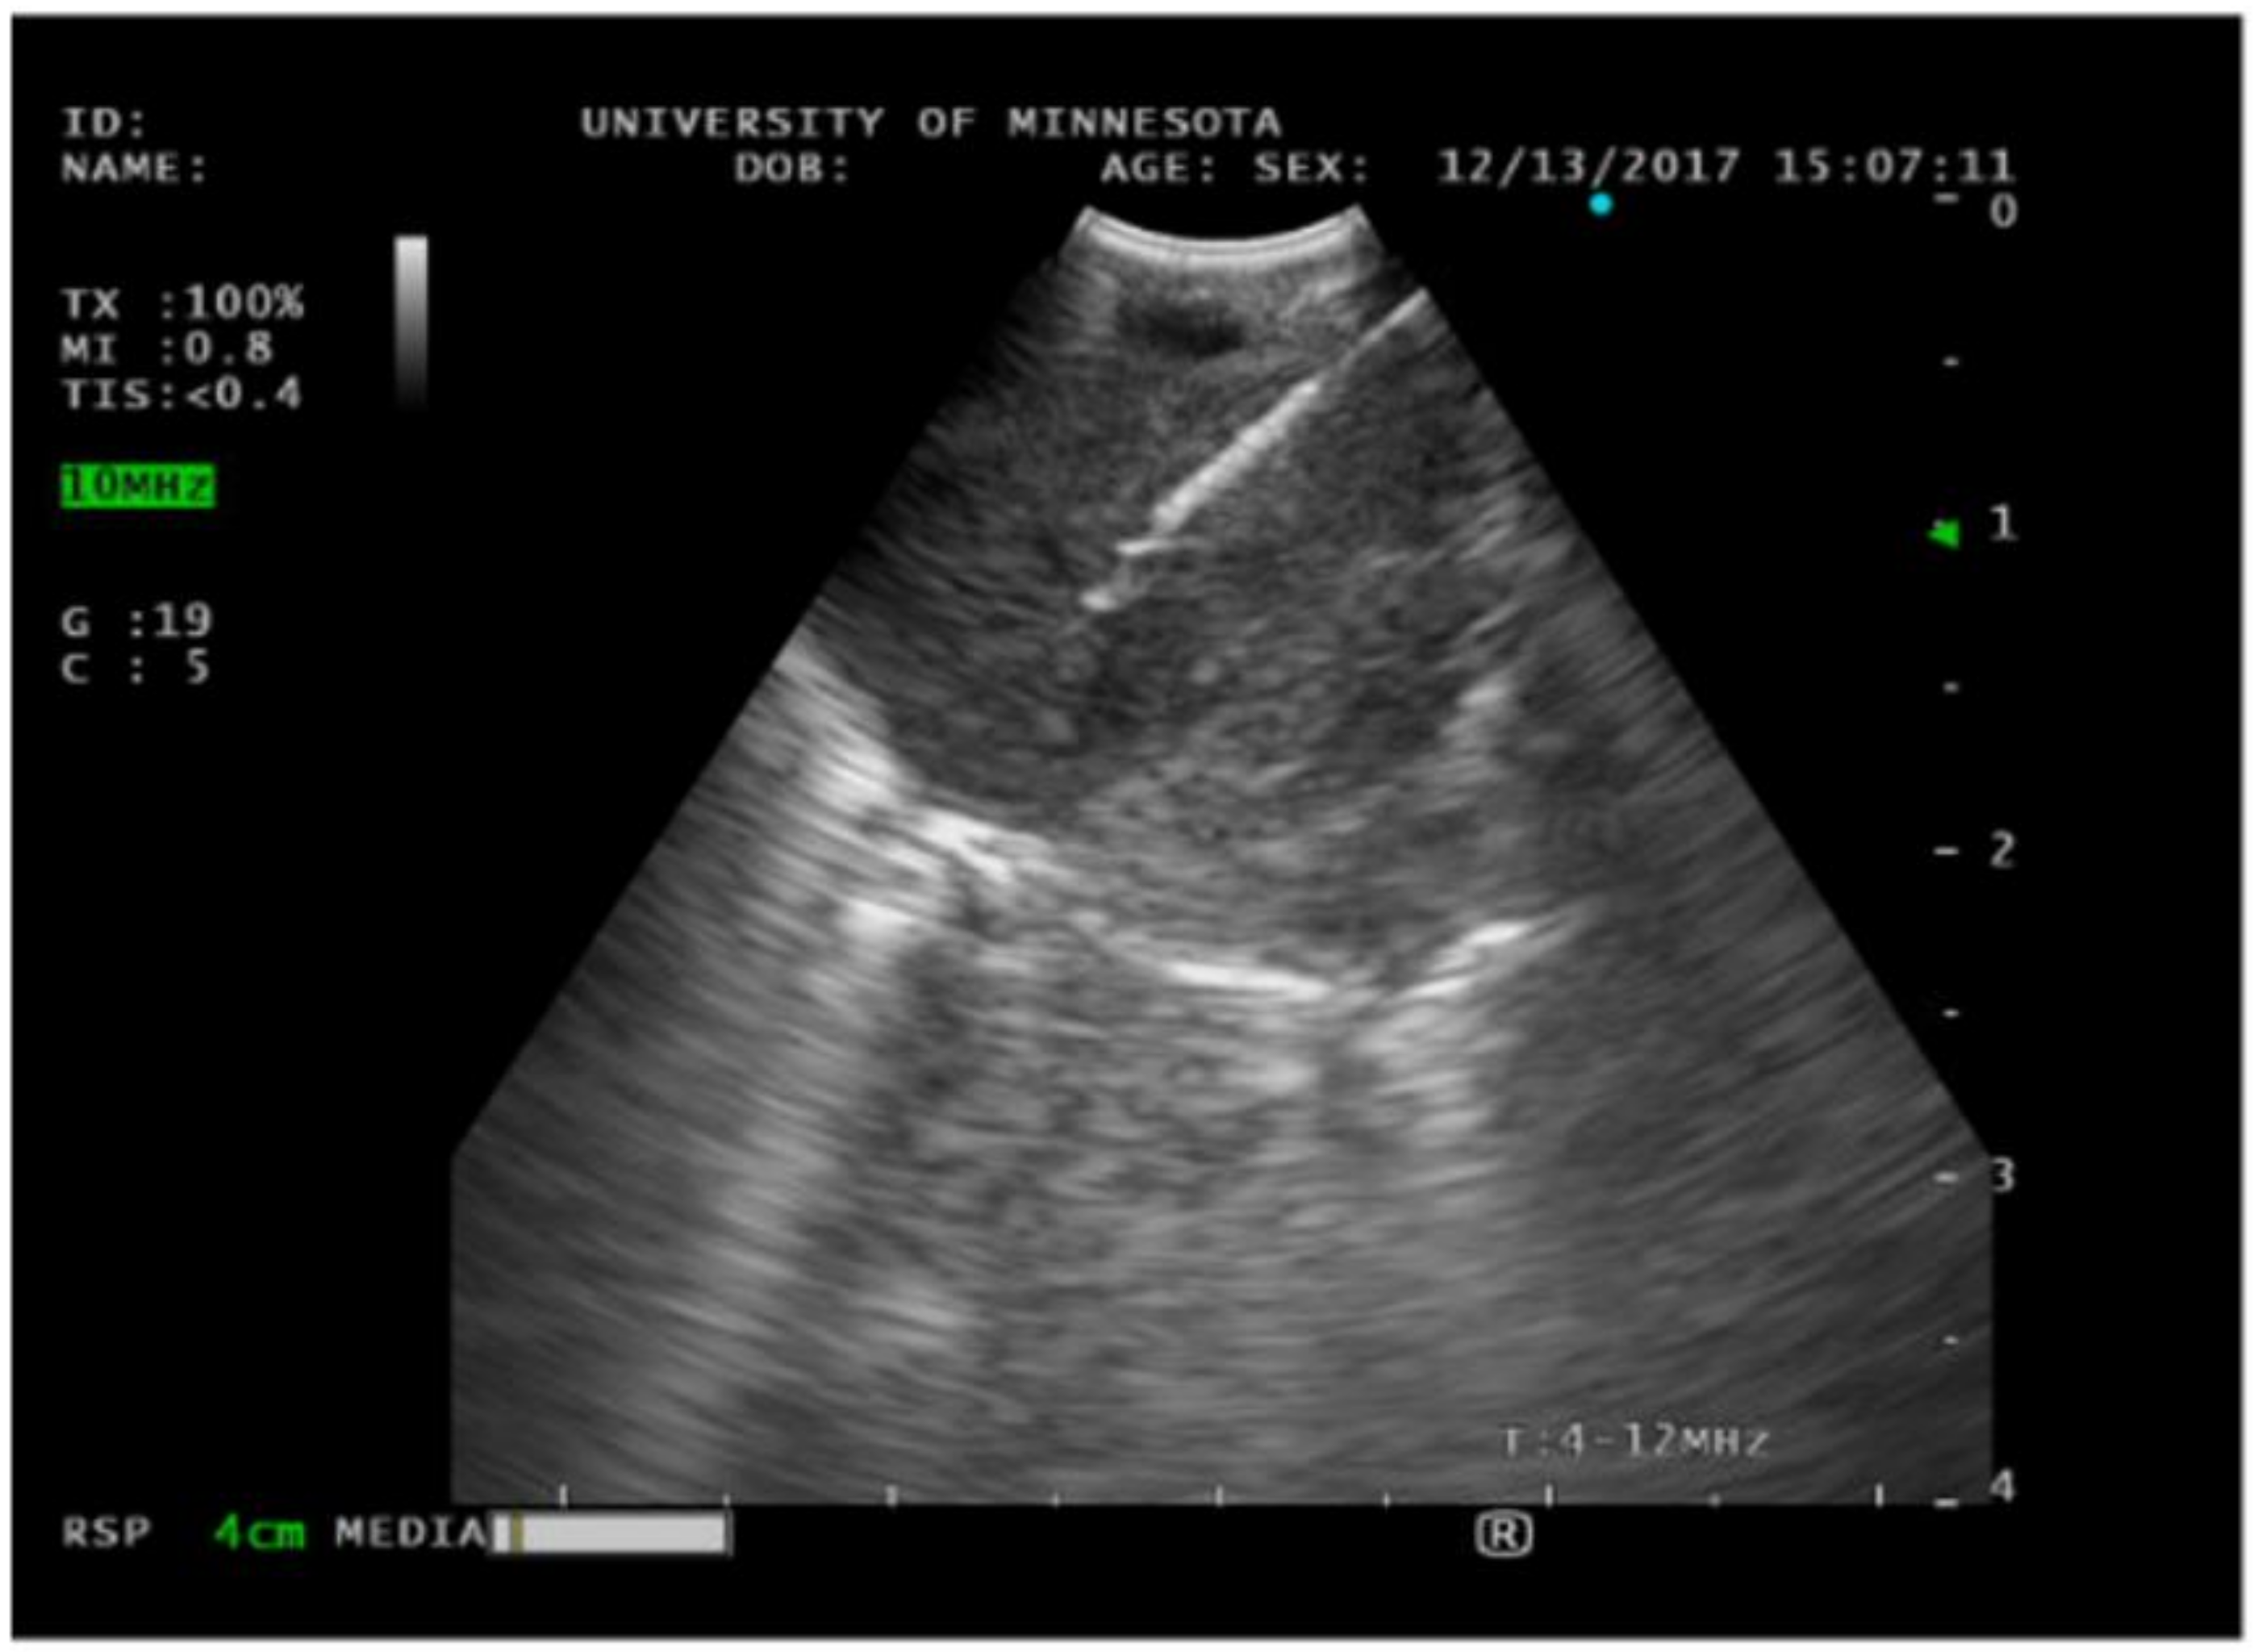

2.4. Endobronchial Ultrasound